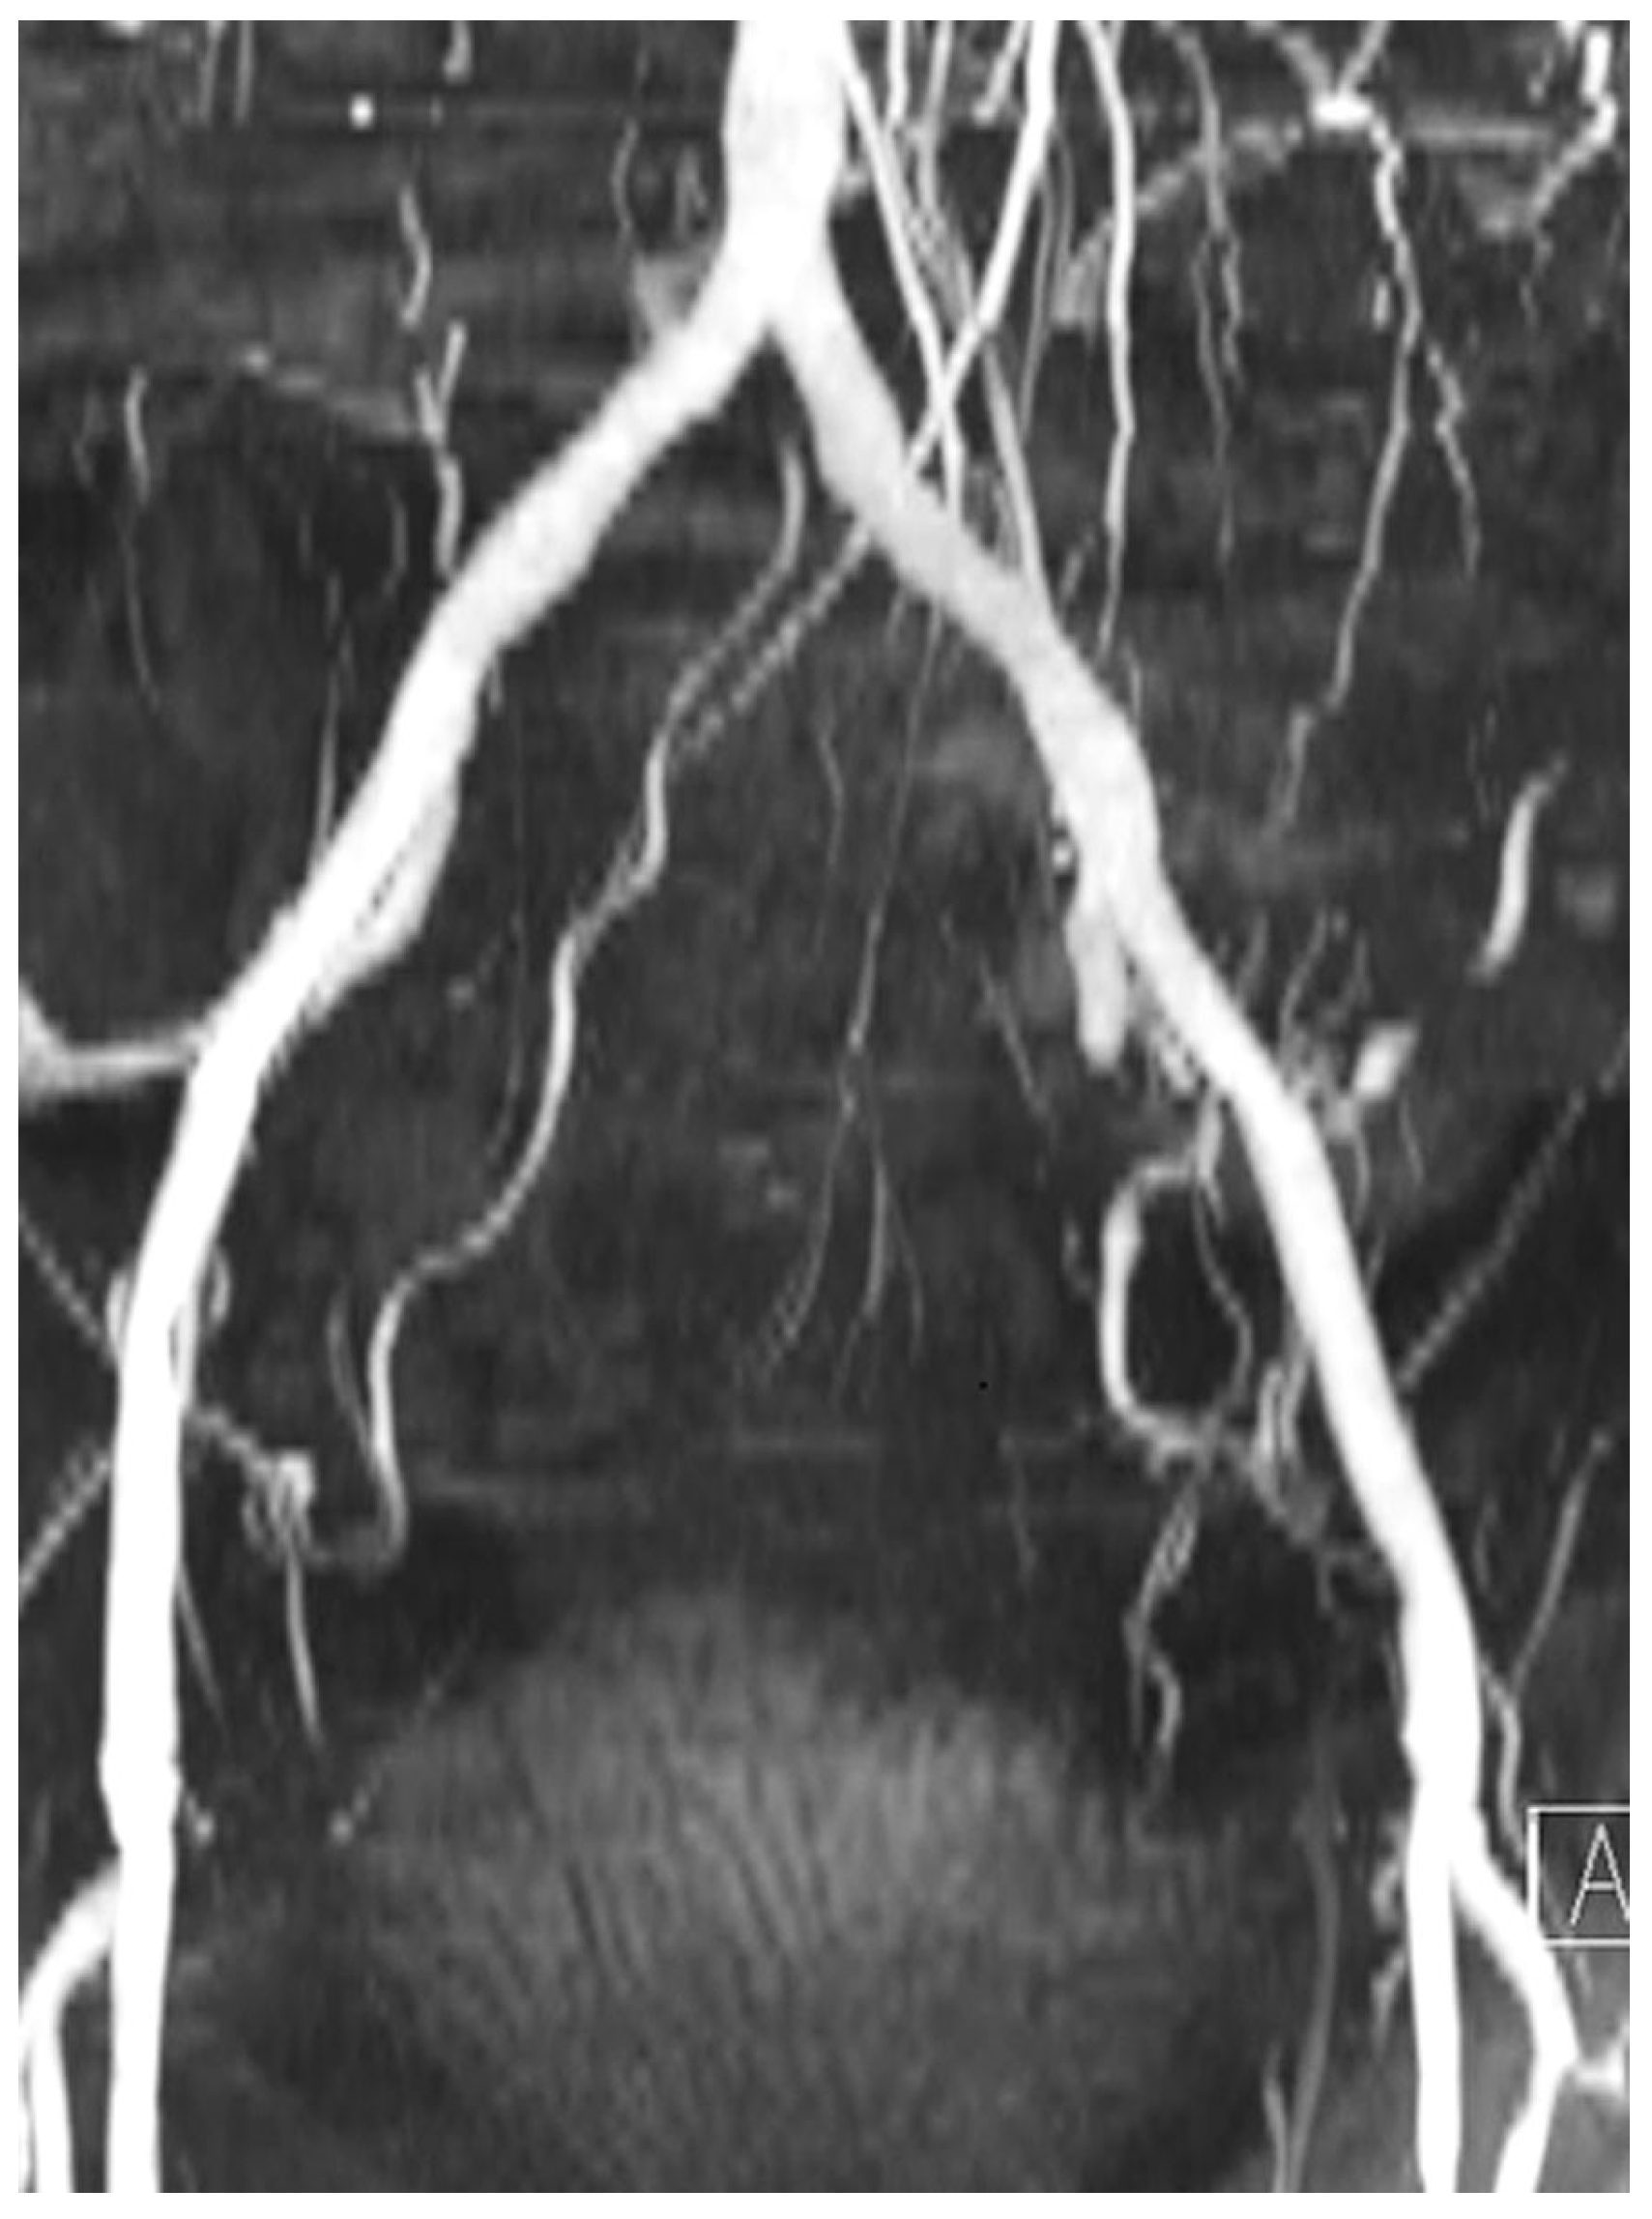

- Bernhardt, P.; Rodewald, C.; Seeger, J.; Gonska, B.; Buckert, D.; Radermacher, M.; et al. Non-contrast-enhanced magnetic resonance angiography is equal to contrast-enhanced multislice computed tomography for correct aortic sizing before transcatheter aortic valve implantation. Clin Res Cardiol. 2016, 105, 273–278. [Google Scholar] [CrossRef] [PubMed]